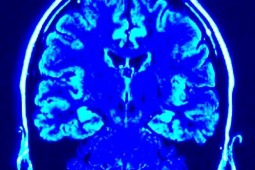

Identyfikacja choroby Azheimera

Hiszpańscy badacze zidentyfikowali właśnie marker, który jest obecny w płynie mózgowo-rdzeniowym i który pozwoli na łatwiejsze i szybsze diagnozowanie i leczenie choroby Alzheimera. I to aż 10 lat przed pojawieniem się objawów tych problemów neurodegeneracyjnych.

Hiszpańscy naukowcy udowodnili, że niskie poziomy DNA mitochondrialnego w płynie mózgowo-rdzeniowym są nie tylko przedklicznicznym wskaźnikiem choroby Alzheimera, ale także jedną z jej przyczyn!